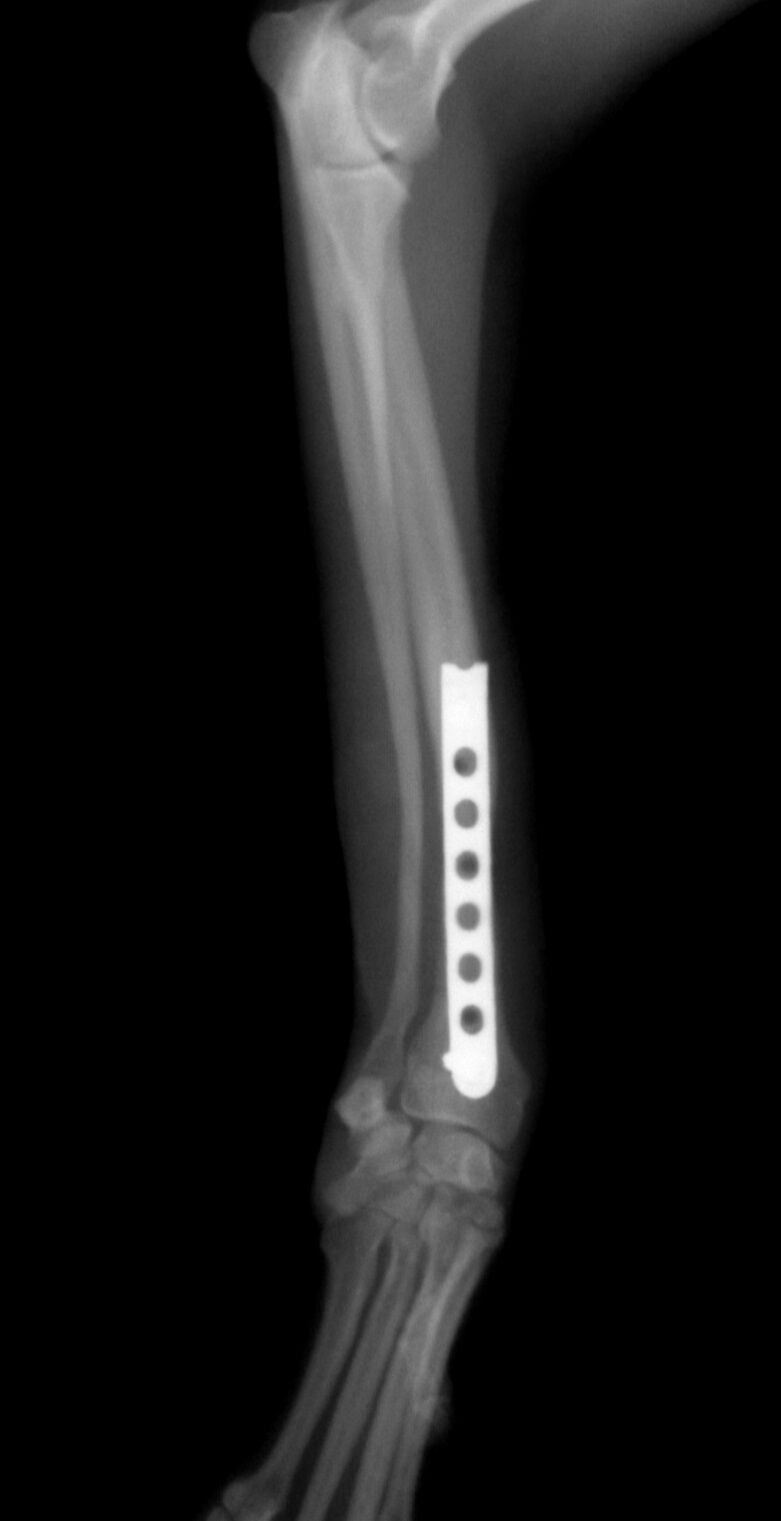

手術後1か月は外固定で補助します。その後、レントゲンで問題ないことを確認し外固定を外しました。外した後は普通に歩行し、散歩なども普段通りにしてもらいます。獣医師によってはプレートを残したままにすることがありますが、中にはプレート部分の骨が細くなってしまうことがあります。もし仮にプレートが折れてしまった時には大変な手術が必要になることがあります。当院では高齢犬であればプレートを残したままにするのですが、この症例は若かったので上記の心配もありますので、プレートを除去することにしました。ただトイ・プードルは骨の増生が良くないことが多いので、プレートを外した直後に再骨折したということがよくあります。ですので、当院ではプレートを留めているスクリューを段階的に外していきます。下の写真は手術後3か月の時に一部のスクリューを取った写真です。

スクリュー除去前 骨折面は消えています。

スクリュー除去後